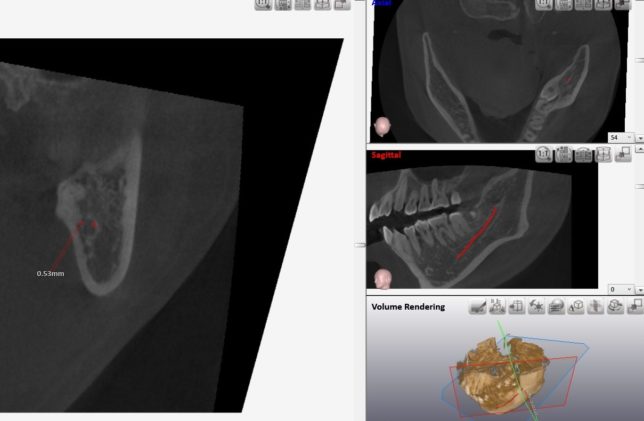

精査のためにCTレントゲン写真を撮影しました。 左下の親知らずは、ほとんどが骨に埋まっています。

更に詳細を分析します。

赤いチューブのような線は、下顎管といわれる動脈と神経で、親知らずの根の先と、かなり距離が近いです。

CTの角度を変えて、親知らずと下顎管の距離を計測します。

その距離、およそ2.3mm

ここまで下顎管との距離が近いと、親知らずを抜く際に、神経や動脈を損傷するリスクがあります。